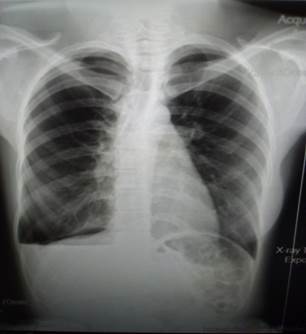

Radiografía digital de tórax vista PA (Figura 2), realizada durante el ingreso: se observó hidroneomotórax derecho.